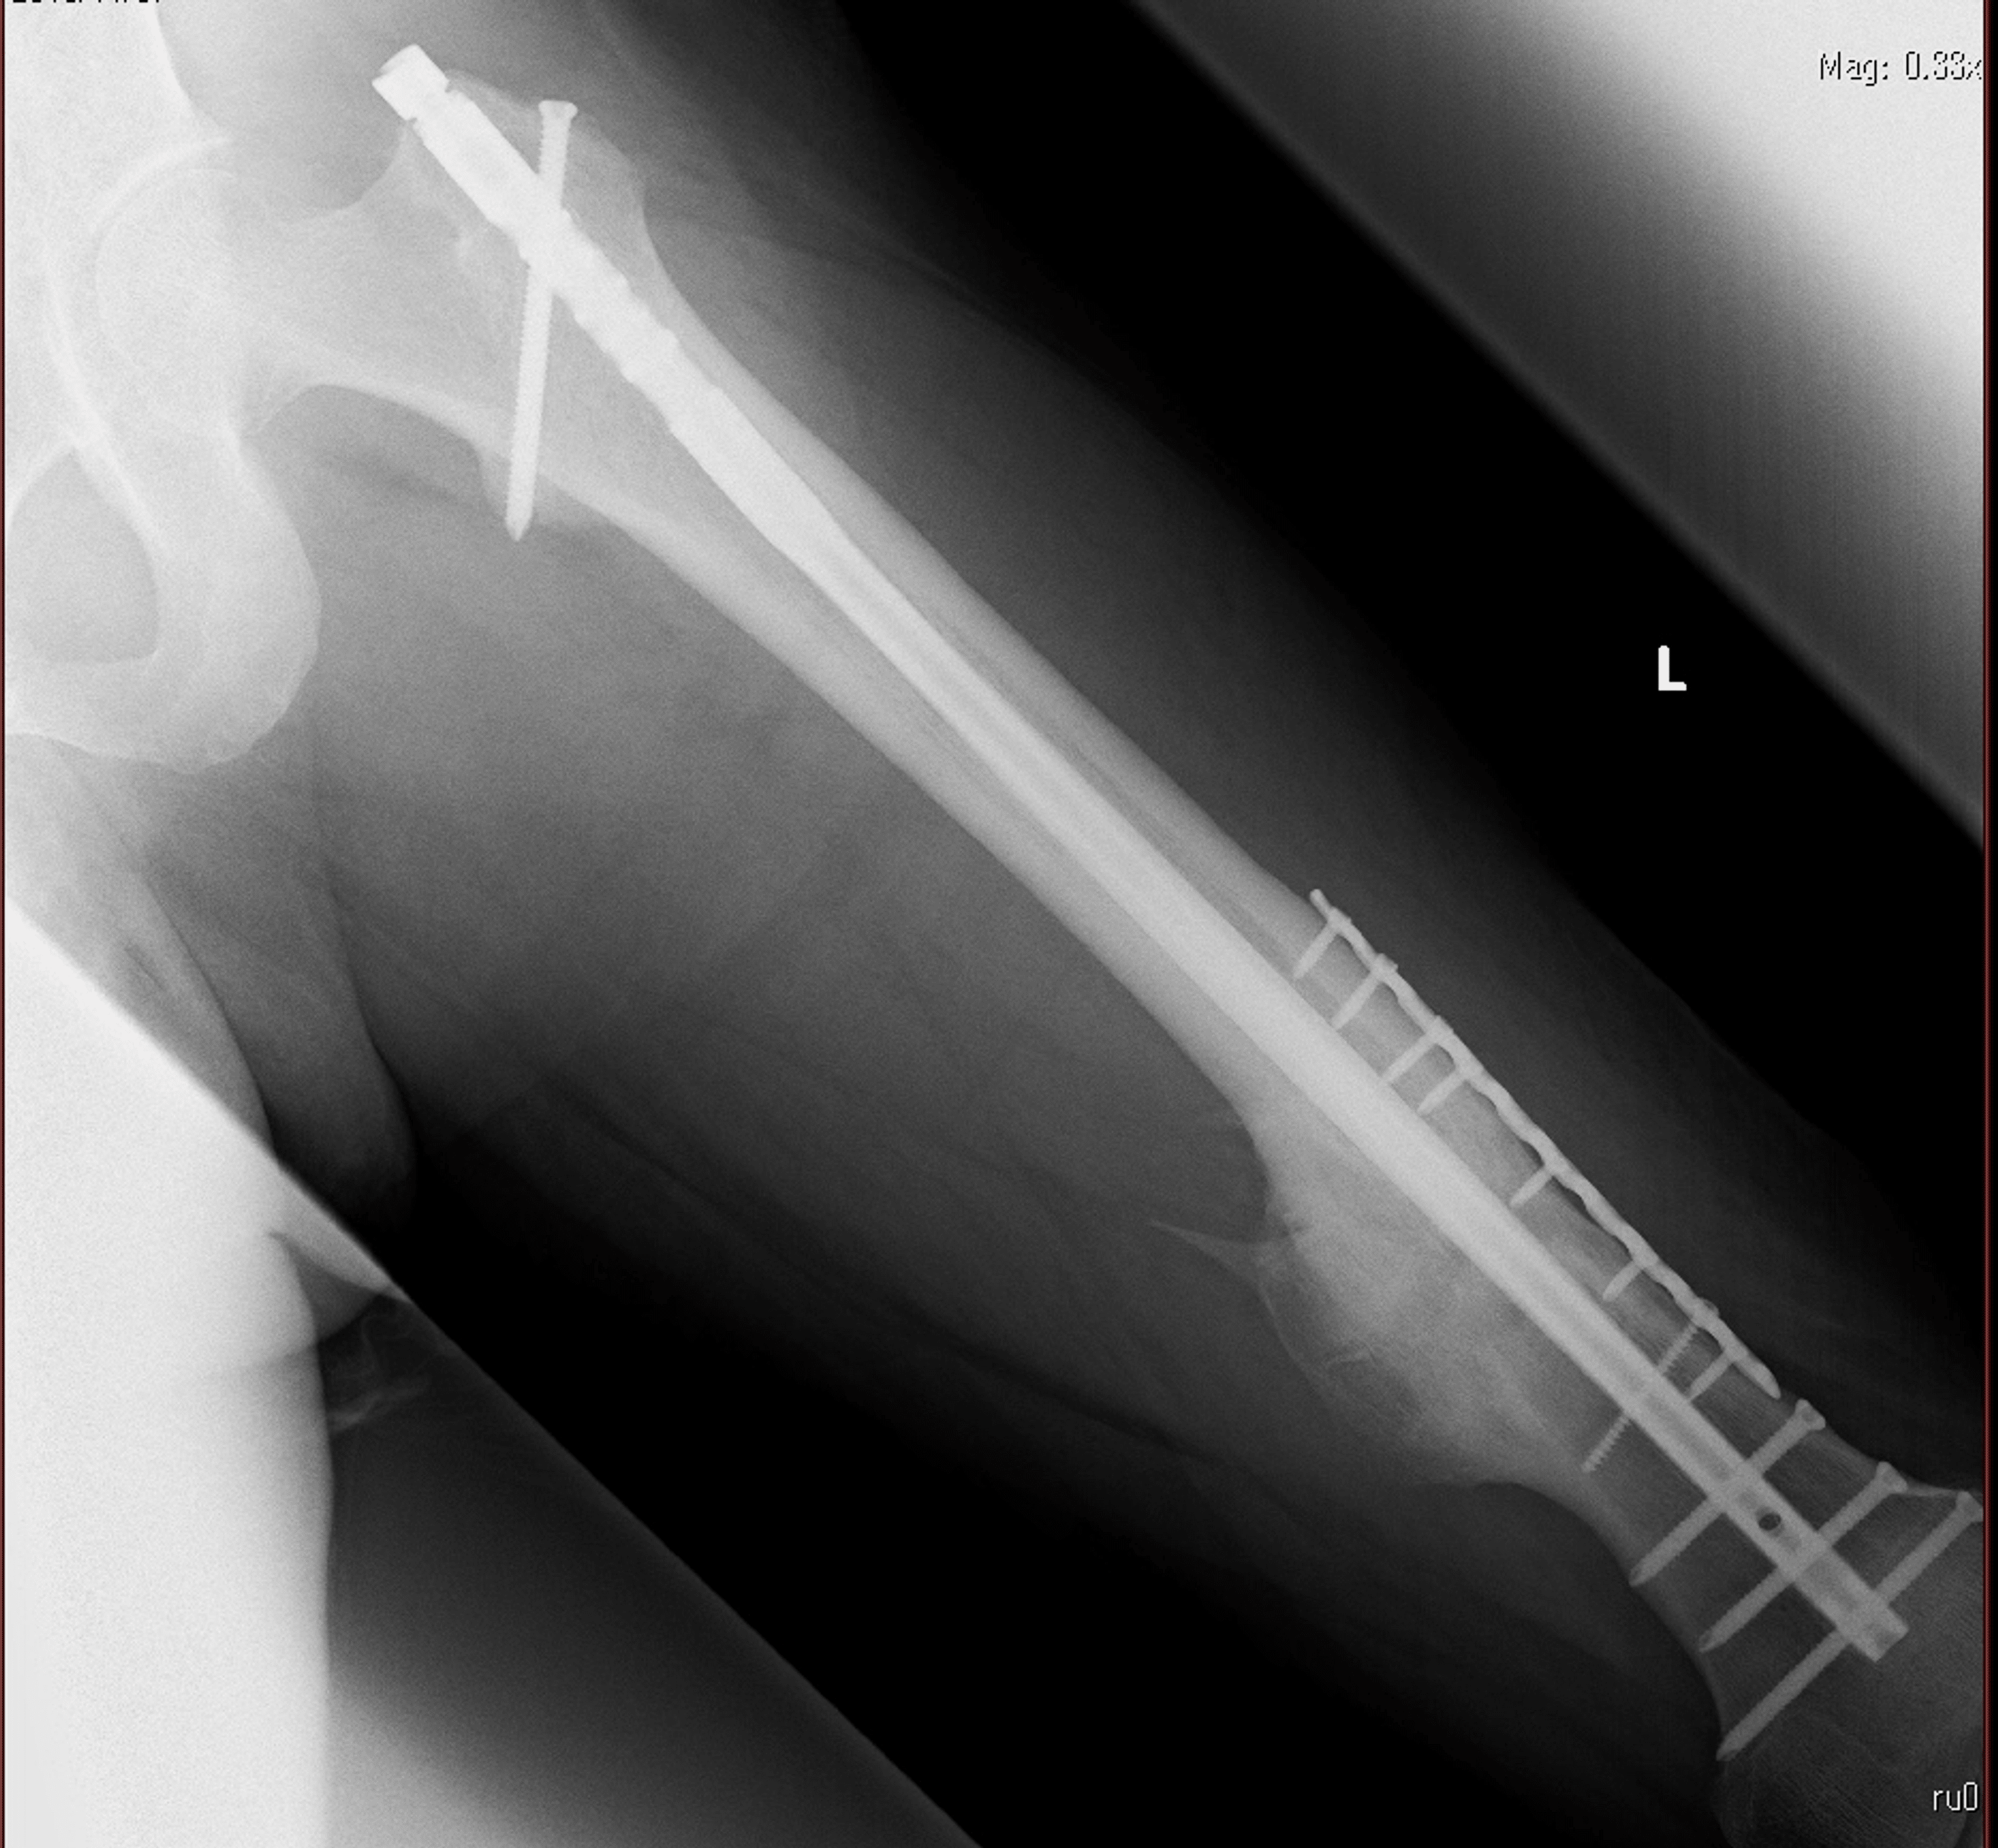

Gluteal Compartment Syndrome After Femoral Nail Extraction A Case Report Cureus Gluteal Compartment Syndrome Radiology We present three patients with gluteal compartment syndrome and review the clinical presentation, imaging, and laboratory. Compartment syndrome, an exceptionally rare condition, is a surgical emergency that can quickly escalate to limb. Gluteal compartment syndrome is a potential risk following total hip arthroplasty and is attributed frequently to body habitus and. Acute compartment syndrome is a painful condition caused by. Gluteal Compartment Syndrome Radiology.

Gluteal Compartment Syndrome After Femoral Nail Extraction A Case Report Cureus Gluteal Compartment Syndrome Radiology The gluteal region is a rare anatomic location for the. Gluteal compartment syndrome is an orthopaedic emergency that may be more prevalent and associated with a higher mortality rate (7% inpatient mortality) and. Gluteal compartment syndrome is a potential risk following total hip arthroplasty and is attributed frequently to body habitus and. Gluteal compartment syndrome is a rare, often unrecognized. Gluteal Compartment Syndrome Radiology.

Gluteal Compartment Syndrome After Femoral Nail Extraction A Case Report Cureus Gluteal Compartment Syndrome Radiology Gluteal compartment syndrome is a rare, often unrecognized syndrome that may. Gluteal compartment syndrome is a potential risk following total hip arthroplasty and is attributed frequently to body habitus and. Gluteal compartment syndrome is an orthopaedic emergency that may be more prevalent and associated with a higher mortality rate (7% inpatient mortality) and. Gluteal compartment syndrome is an orthopaedic emergency. Gluteal Compartment Syndrome Radiology.